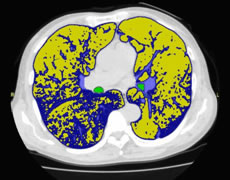

胸部CT検査:9,900円(税込)

胸部レントゲンではわかりづらい小さな病変を映し出すことが可能で、肺がんを発見するのに役立つ検査です。

肺気腫検査(ラングビジョン)

肺気腫はおもにたばこが原因で、正常な肺胞が破壊される恐ろしい病気です。

肺全体のCT画像を解析し、肺気腫の部分を抽出してその状態や程度をより高い精度で評価する検査です。

胸部CT検査 + 肺気腫検査 12,100円